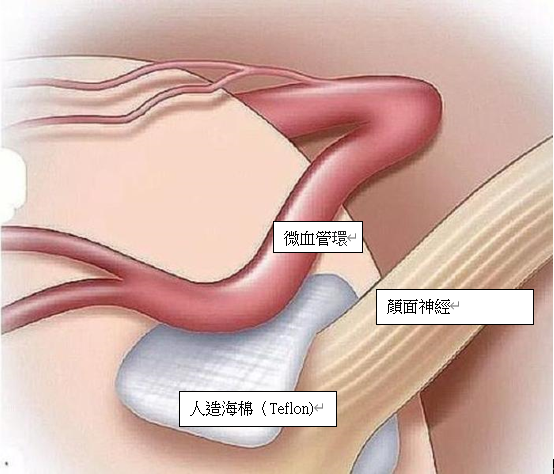

全身麻醉下, 脑神经外科医生会在显微镜下, 在病人耳后的颅底骨进行手术, 手术并不是在大脑内部进行操作,而是利用人体组织的间隙、在脑组织与颅骨之间的蛛网膜下腔内进行手术, 因此不需要破开任何脑神经。脑神经外科医生会将压迫着颜面神经根部的血管隔开,并以人造海棉(Teflon) 将血管与神经永久阻隔,去除神经线短路的因由。手术的治愈率达到80-90%上,复发率约10%,严重的并发症 (如听觉神经功能失聪) 的风险的发生率侧为2%。